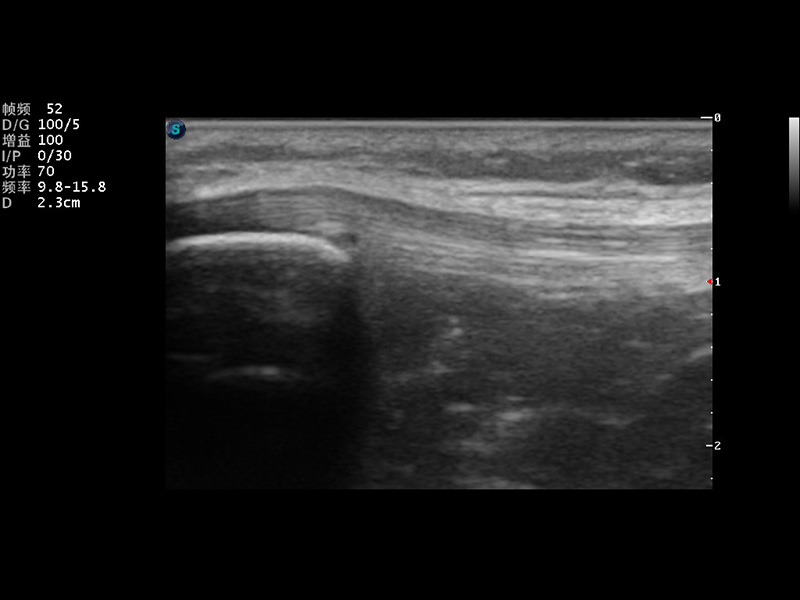

S9便携式彩色多普勒超声诊断仪是球速体育入口研发的高端便携彩超设备,外观设计新颖、产品性能卓越。S9在便携超声领域采用了突破传统的触摸屏交互设计,并以先进的软件硬件技术和设计理念,为您带来清晰的图像质量、稳定的工作性能和便捷的操作体验。

成像技术

μ-Scan微米成像